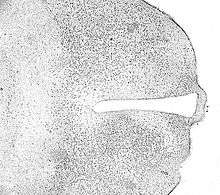

IHC is an excellent detection technique and has the tremendous advantage of being able to show exactly where a given protein is located within the tissue examined. It is also an effective way to examine the tissues. This has made it a widely used technique in the neurosciences, enabling researchers to examine protein expression within specific brain structures. Its major disadvantage is that, unlike immunoblotting techniques where staining is checked against a molecular weight ladder, it is impossible to show in IHC that the staining corresponds with the protein of interest. For this reason, primary antibodies must be well-validated in a Western Blot or similar procedure. The technique is even more widely used in diagnostic surgical pathology for immunophenotyping tumors (e.g. immunostaining for e-cadherin to differentiate between DCIS (ductal carcinoma in situ: stains positive) and LCIS (lobular carcinoma in situ: does not stain positive)[5]). More recently, Immunohistochemical techniques have been useful in differential diagnoses of multiple forms of salivary gland, head, and neck carcinomas.[6]